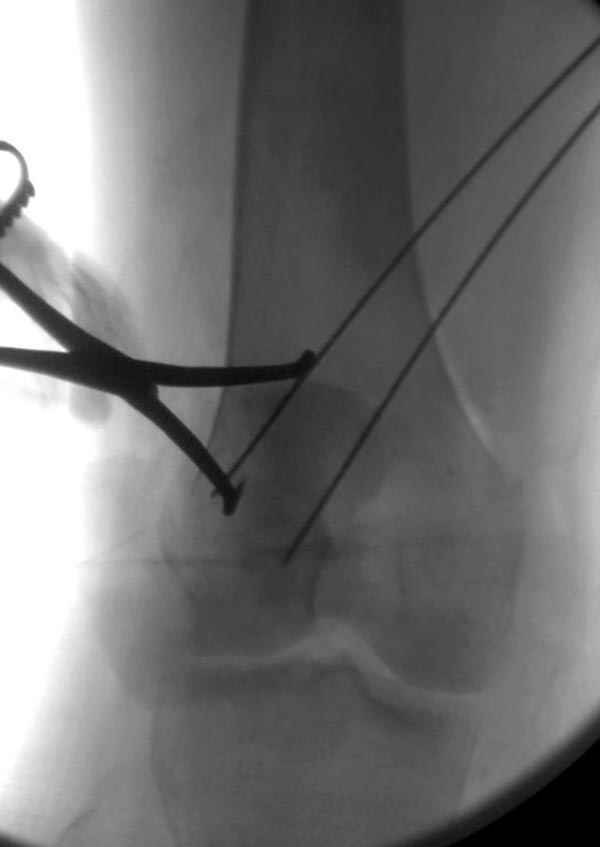

На операции: Irrigation&Debridment около 10 литров раствора, по два стержня в сегменте, фиксация диагонального, с дефектом, перелома надколенника тремя cannulated 4мм шурупами, ушивание поперечного разрыва связки 5.0 Ethibon sutures, разрыв находился на 2 см ниже надколенника (срез чем-то острым), повторная ирригация раны, взятие посева на аэробическую и анэробическую культуру, окончательная фиксация стержней наружного фиксатора 50см Carbon Fiber Bars, вакуумное закрытие. Мониторинг показал, что компартмент синдрома нет.

Сегодня досылаю остальные снимки, которые не прошли вчера. Как вчера писал, после фиксации перелома надколенника с дефектом кости и собственной связки, наложили ваккуум и наружный фиксатор. (снимки 4-9)

Внешний фиксатор держим около 6 недель, поэтому был выбран метод фиксации шурупами и еще линия перелома была диагональной, не было нужды в tension band technique, cannulated screws удобнее, провел спицы и по ним шурупы.

На слайдах (не четко обозначены бедро и голень): на бедре по наружно-передней поверхности, между вастус латералис и прямой головками, а на голени по передне-медиальной поверхности, желателен подбор длины резьбовой части стержня по ширине поперечника кости. На снимке: дистальное кольцо, метод проведения стержня через канюлю-проводник.